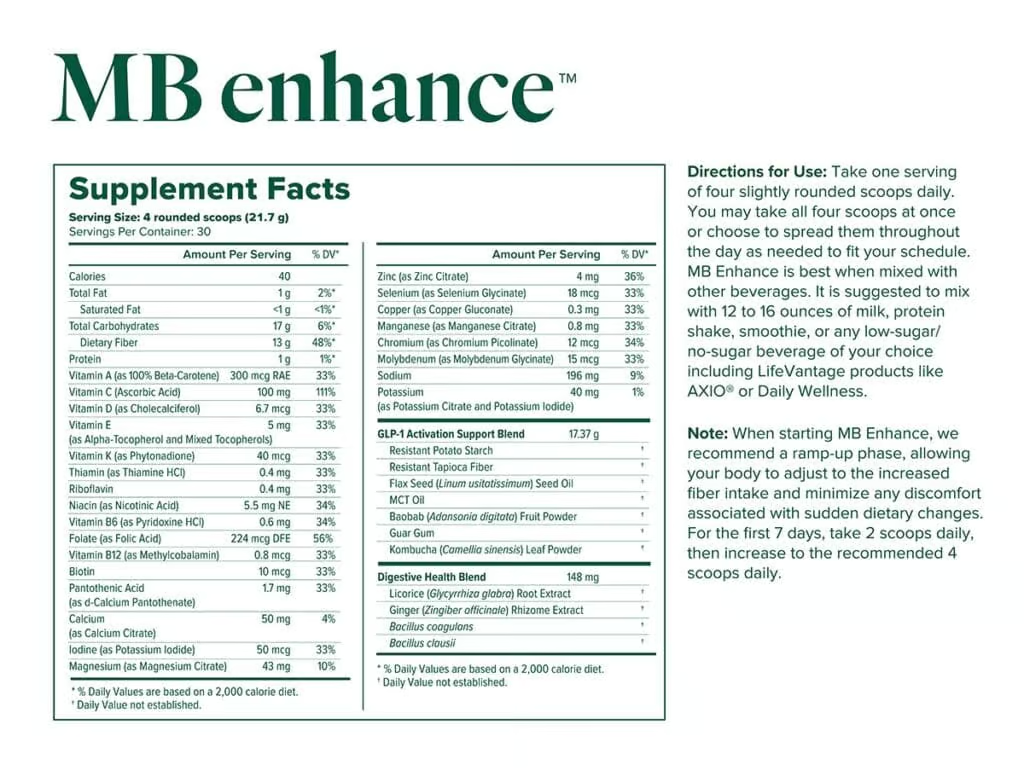

Los ingredientes de MindBody GLP-1

Información sobre los suplementos MB core y MB enhance